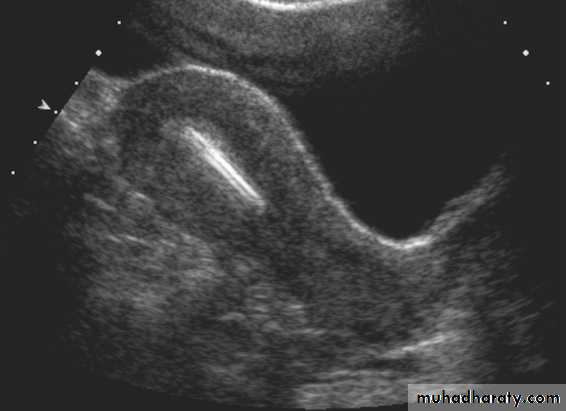

Transabdominal scanned image

• Rupture of hemorrhagic ovarian cyst:

Transvaginal scanned image